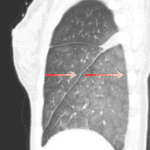

Indication: Hypoxia, dyspnea

CT

Sample ReportPulmonary edema with a small right pleural effusion.